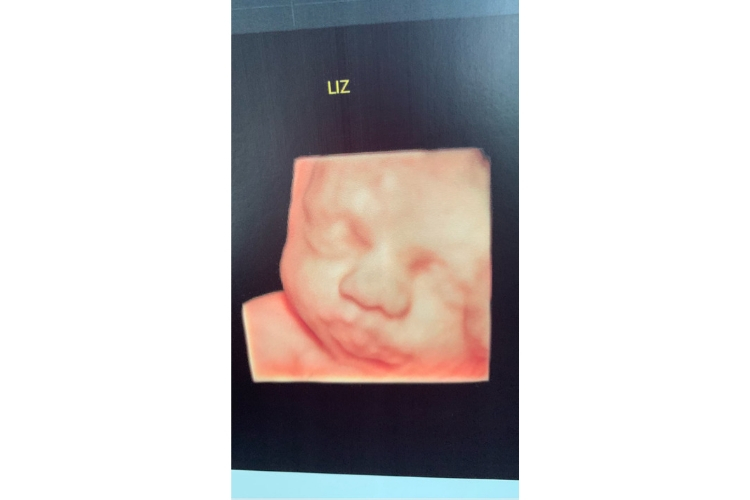

A cantora Thaeme surpreendeu os fãs na manhã desta quinta-feira (28). A sertaneja que está grávida de Liz, fruto de seu casamento com o empresário Fábio da Lua, compartilhou em suas redes sociais uma foto do ultrassom onde é possível ver o rostinho da bebê.

Thaeme, que recentemente surpreendeu os seguidores ao mostrar o tamanho de seu barrigão, compartilhou a imagem na ferramenta stories de seu Instagram.

Confira: